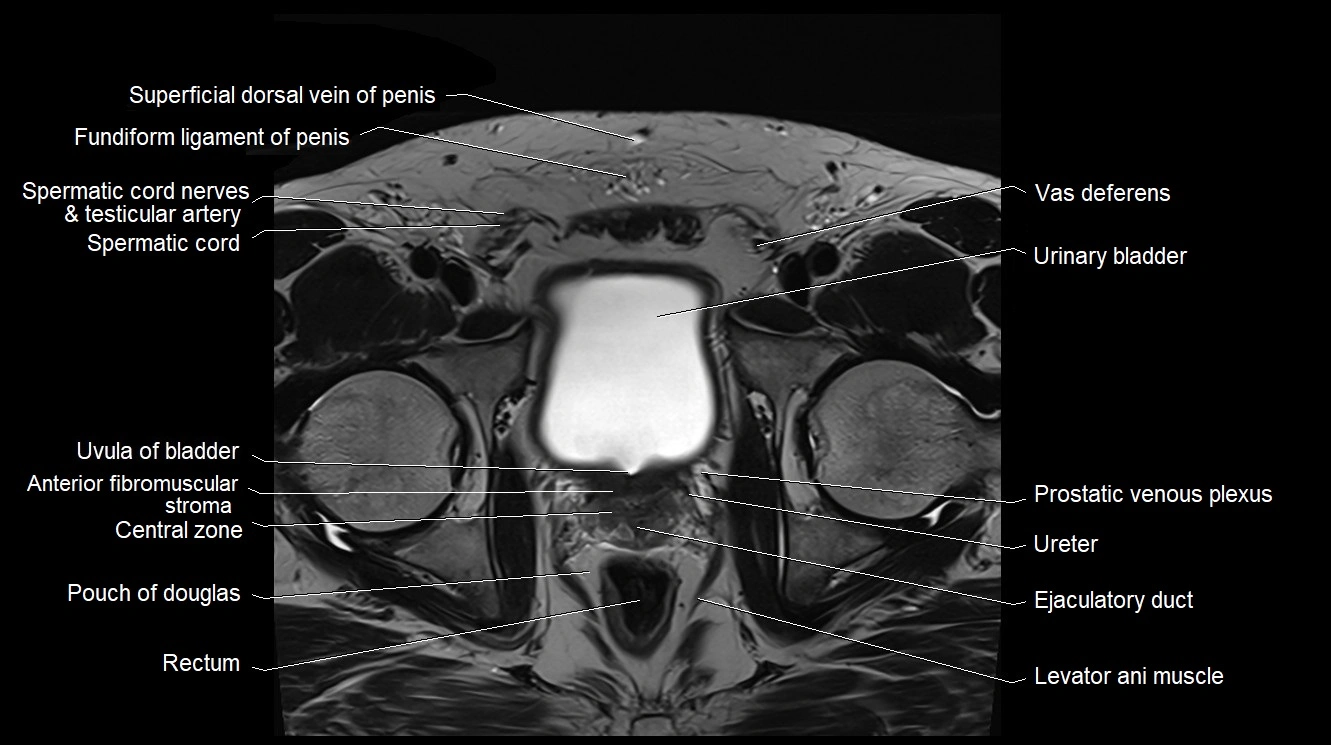

MRI image